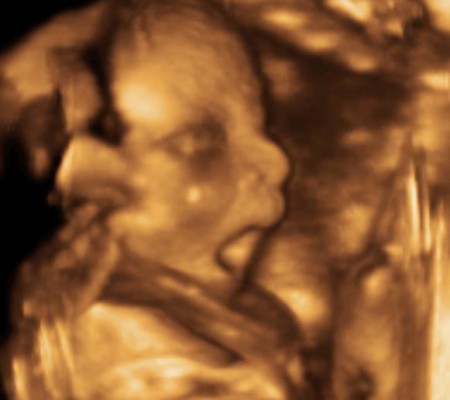

Kao i 2D, 3D i 4D koriste ultrazvučni talas da se kreira slika bebe u materici. 3D je kreirana slika u prostoru dok 4D prikazuje pokret unutar materice pa možemo videti kako se beba smeje, mršti ili zeva.

Za prikaz ovih preseka potrebni su odgovarajući uslovi kao što su položaj ploda (lice ka nama), normalna količina plodove vode, poželjno je da ruke, noge i pupčanik ne budu ispred bebinog lica. U neodgovarajućim uslovima ovaj snimak nije moguće napraviti.

Da bi se dobile dobre slike poželjno je da se pregled radi između 24 i 32 nedelje trudnoće.